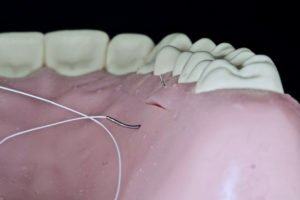

No caso descrito acima, para a sutura da área doadora no palato, optou-se por agulhas 1/2 de círculo, 13 mm de comprimento e com o corte triangular reverso para a área doadora do palato (Figura 5A e B). Na região palatina, este formato permite que a distância entrada da agulha seja a mesma da saída da agulha. As agulhas com o formato 3/8 de círculo tendem a sair no interior do sulco gengival e pode causar traumatismo e posterior recessão gengival na região do dente doador. Outro aspecto é a permanência do fio de sutura no interior do sulco gengival. Fios de

sutura com grande capilaridade – normalmente os multifilamentares – podem servir de reservatório bacteriano e causar um possível inflamação gengival no pós-operatório.

Figura 5A e B – Sutura realizada na região doadora do palato. Observar a seleção da agulha: 1/2 de círculo, 13 mm de comprimento e corte triangular reverso. Esse formato permite que a distância entrada da agulha seja a mesma da saída da agulha.